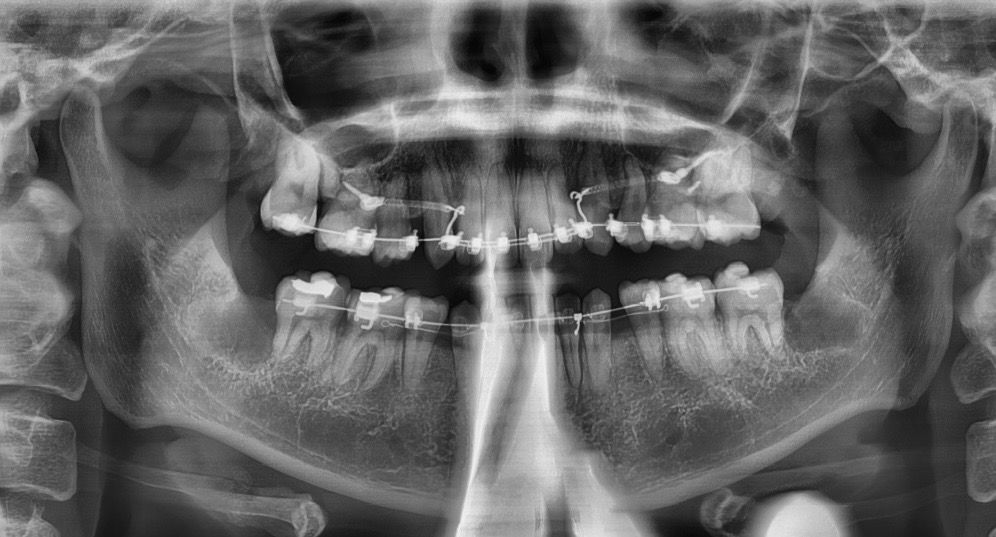

파노라마는 얼마전 사랑니 발치전후에 찍은 사진으로 한달간격으로 찍었습니다. 몇달전부터 오른쪽 어금니(파노라마상 왼쪽 어금니)가 씹을때마다 불편했는데 파노라마를 찍어보니 다른 부분이랑 조금 다르게 조금 큰 까만 세로 선이 보여서 혹시 제가 씹을때 불편한것과 관련이있을까 싶어 여쭤봅니다. 왜 이럴까요..?

다른치료로 다른 치과에 방문했을때 저것이 치주인대부분이다. 저렇게찍힐수있다라는 말만 하시긴하셨어요.

교정치료중 치아가 이동하며 생길수있는 증상이라 시간이 지나면 괜찮아질 것으로 예상됩니다.

치아를 이동시키게 되면 치아의 인대가 늘어 나면서 저렇게 진하게 보이는 경우가 발생합니다.

치아와 잇몸뼈 사이 치주인대가 있는 곳이고 염증이 있으면 그 공간이 넓어져서 엑스레이상에 보입니다